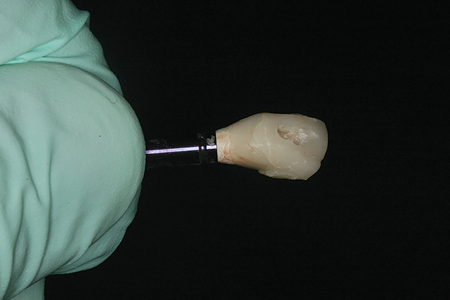

After three months and receiving restorative clearance from the oral surgeon (osseointegration confirmed by the oral surgeon), the patient was appointed to begin the restorative process. The bonded provisional was removed and a stock screw retained temporary implant post was modified with composite to develop proper emergence profile. Composite was bonded to the temporary post radially below the height of contour to pressure the tissue and emulate a tooth prepared for a crown restoration. (Fig. 8) When the desired initial tissue support was achieved, the composite on the provisional post was polished and the post was screwed into place. The access hole of the temporary post was filled with teflon tape prior to fabrication of a bisacrylic provisional crown. A polyvinyl siloxane stent made from the diagnostic waxup was filled with B1 Luxatemp Ultra (DMG America; Ridgefield Park, NJ) and placed over the prepared abutment and allowed to cure. After approximately 1 minute, the stent was gently removed with the bisacrylic provisional remaining inside. The provisional was removed from the stent, trimmed, and bonded with Optibond FL resin (Kerr Corp; Orange, CA) to the provisional abutment. (Fig. 9) The provisional crown was cured for 30 seconds with the Bluephase LED curing light (Ivoclar Vivadent; Amherst, NY). Excess material was removed with a #12 scalpel blade, and the provisional was smoothed and finished with abrasive discs (Cosmedent Inc.; Chicago, IL) and a rubber cup polisher (Cosmedent Inc.; Chicago, IL). The tissue was then allowed to heal and adapt to the temporary structure for a period of two weeks.

Fig. 8

Fig. 9